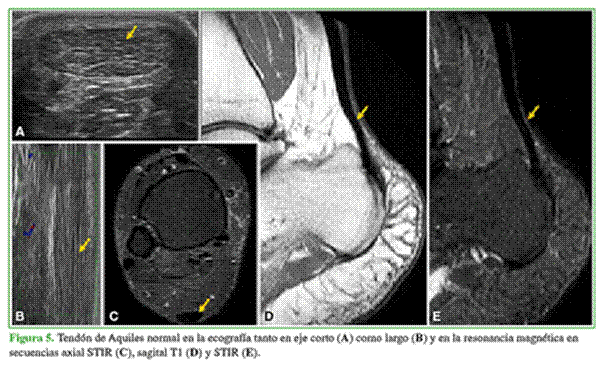

En la ecografía, un tendón normal muestra ecos lineales brillantes paralelos con transductor lineal con frecuencia de 10 ± 22 MHz. La ecogenicidad es causada por la reflexión en las interfases entre los haces de colágeno (Figura 5). La elastografía es una técnica asociada a la ecografía que permite valorar la elasticidad de los tejidos. Los tejidos que pierden agua se vuelven más rígidos y la elastografía lo demuestra perfectamente.

Los tendones normales en la RM muestran baja señal en secuencias T1 y T2, esto se debe a que son estructuras con bajo componente acuoso. En pacientes con tendinopatías reactivas, se detectan cambios focales en el área afectada mediante la ecográfica o la RM (Figura 6).